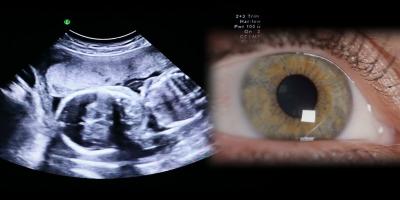

Just as ultrasound makes a developing fetus visible in utero, a wearable ultrasound device may be able to generate sound waves to stimulate the retina to produce vision. Credit: Envatoelements